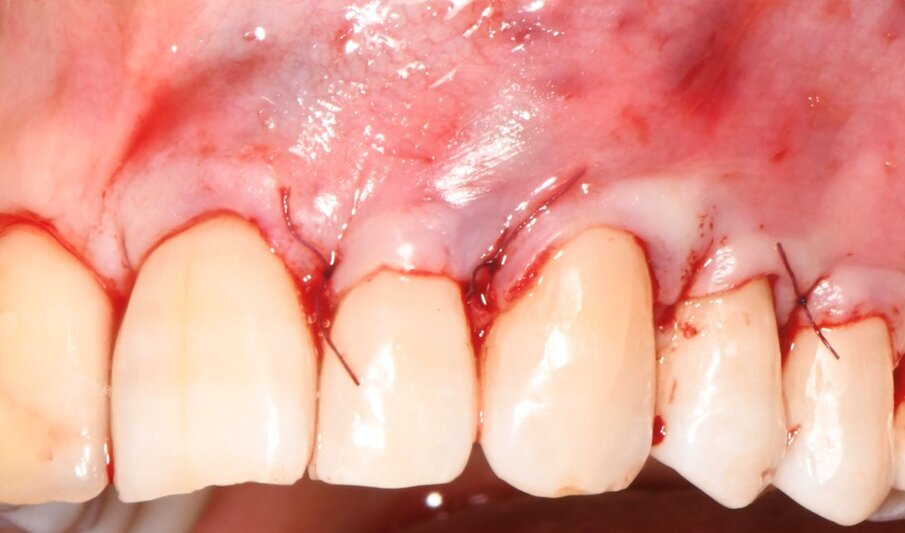

Il caso riguardava un paziente maschio di 38 anni, non fumatore, non affetto da parodontite, che si presentava nello studio per la risoluzione di una recessione gengivale a carico dell’elemento 23, trattato precedentemente con materiale composito (Fig. 1). L’esame clinico evidenziava recessioni multiple nei 4 quadranti associate a lesioni cervicali non cariose (NCCLs). In particolare, erano presenti recessioni gengivali di tipo I a carico degli elementi 21-25 (Fig. 2). Le gengive erano caratterizzate da un fenotipo sottile. Previo trattamento conservativo delle NCCLs eseguito nella settimana precedente a quella dell’intervento, veniva ripristinata la sede della giunzione smalto-cemento in sede 21-25. In accordo con il paziente si conveniva di trattare le recessioni gengivali di tipo I degli elementi 23-25 con una procedura di chirurgia mucogengivale che combinava la tecnica del lembo a posizionamento coronale MCAF e l’innesto di una matrice collagenica tridimensionale di origine equina (XC COLLAGEN Xenomatrix, Bioteck Spa). La sede delle recessioni presentava una sufficiente banda di gengiva aderente (2 mm) che consentiva l’impiego della matrice collagenica. L’area di intervento veniva anestetizzata utilizzando articaina cloridrato 40 mg + 10 µg/ml di adrenalina (Citocartin, Molteni Dental s.r.l). L’intervento per la copertura radicolare veniva eseguito con tecnica MCAF individuando il canino come centro di rotazione del lembo (Fig. 3).

Fig. 3 - Dettaglio delle incisioni primarie, realizzate per definire i limiti coronali del lembo e stabilire il canino come centro di rotazione.